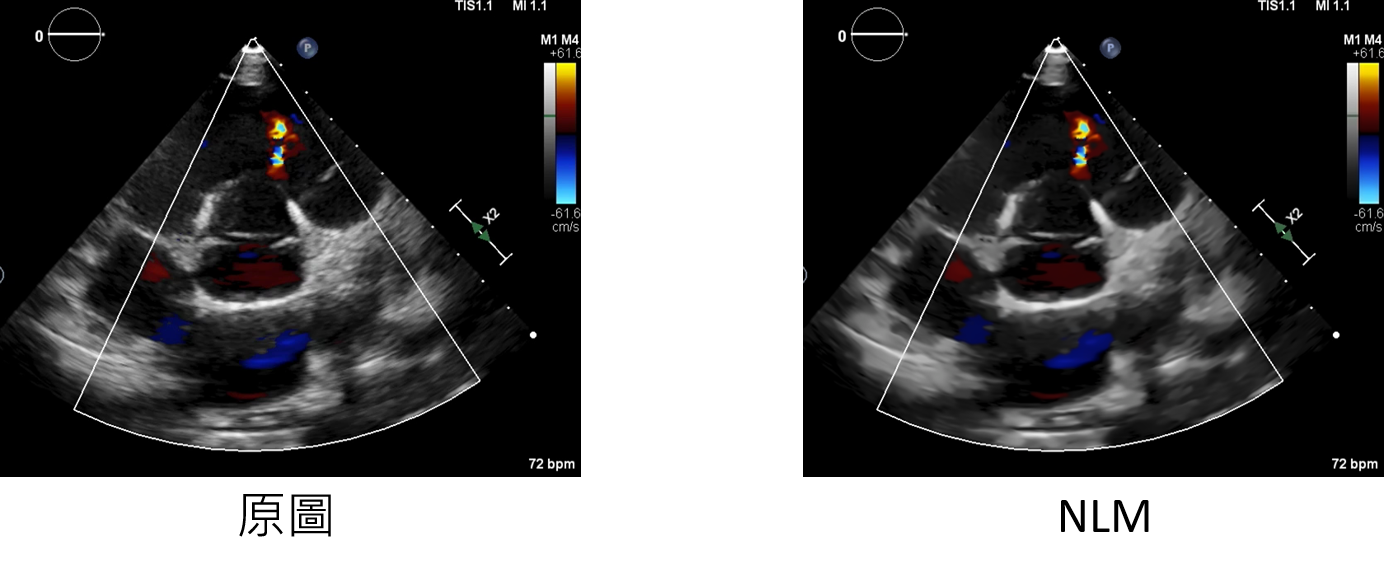

NLM:增強方法

h:決定濾波器強度。較高的值可以更好的消除噪聲,但也會刪除圖像細節

templateWindowSize:奇數(推薦值為7)

searchWindowSize:奇數(推薦值為21)

datagen=CustomDataGenerator(fun="NLMOpening",h=10,templateWindowSize=7,searchWindowSize=21,dtype=int)